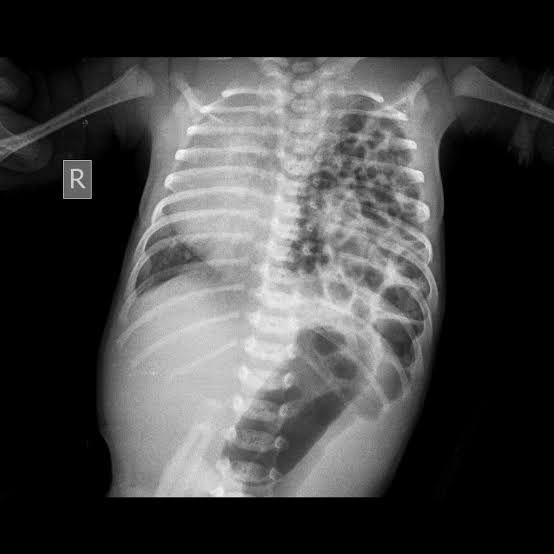

.Mostly in lt side .In CXR : gas filled loops that push heart towrda rt side . Umbo bag may worse the condition .Ttt: ETT + surgical intervention